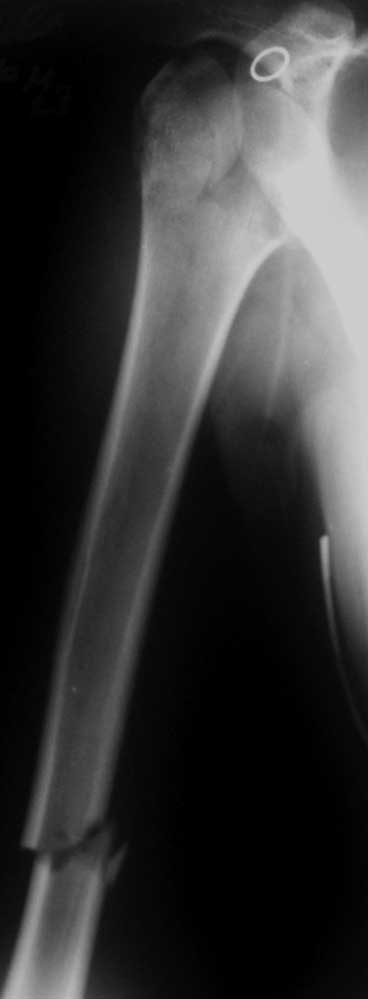

Женщина 23 лет получила травму в результате ДТП (пассажир). Поступила в отделение 07.06.2012 (травма в день поступления).

Диагноз: закрытый перелом шейки правого плеча с отрывом большого бугорка, закрытый поперечный оскольчатый перелом правого плеча на границе средней и нижней трети.При поступлении конечность иммобилизирована задней гипсовой лонгетой от надплечья до головок пястных костей.

Нет смысла мучить пациентку, даже не смотря на юный возраст. От головки ни чего не осталось, собирать нечего, большой процент импрессии и дефекта головки. Диафиз собирать пластиной или штифтом. На в\з плеча либо реверсивный протез - даст больше объема движений,но ревизия в дальнейшем сложней, либо однополюстной.

эндопротез и пластина. на томограмме - перелом головки плеча, синтезировать такое не получится

В любом случае 23-летней пациентке надо сохранять свой плечевой сустав. То есть планировать открытую репозицию. Похоже, сломана только часть головки, так что повреждение не самое худшее. Бугорки на месте. Чем фиксировать - дело десятое. Хоть спицами. Можно и гвоздем из-за дистального перелома. Пластиной - не уверен, что есть смысл, перелома шейки нету здесь.